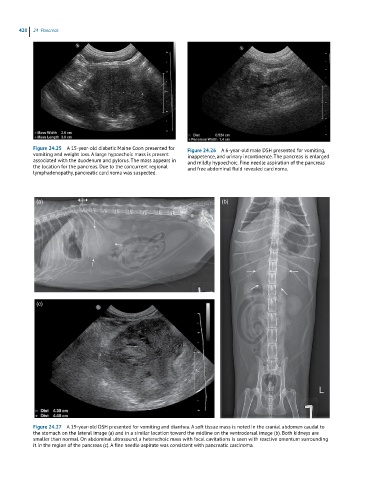

Figure 24.25 A 15-year-old diabetic Maine Coon presented for Figure 24.26 A 6-year-old male DSH presented for vomiting,

vomiting and weight loss. A large hypoechoic mass is present inappetence, and urinary incontinence. The pancreas is enlarged

associated with the duodenum and pylorus. The mass appears in and mildly hypoechoic. Fine needle aspiration of the pancreas

the location for the pancreas. Due to the concurrent regional and free abdominal fluid revealed carcinoma.

lymphadenopathy, pancreatic carcinoma was suspected.

Figure 24.27 A 19-year-old DSH presented for vomiting and diarrhea. A soft tissue mass is noted in the cranial abdomen caudal to

the stomach on the lateral image (a) and in a similar location toward the midline on the ventrodorsal image (b). Both kidneys are

smaller than normal. On abdominal ultrasound, a heterechoic mass with focal cavitations is seen with reactive omentum surrounding

it in the region of the pancreas (c). A fine needle aspirate was consistent with pancreatic carcinoma.